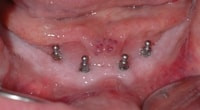

Diese Art der Sofortversorgung bedarf im Unterkiefer mindestens 4 und im Oberkiefer, aufgrund der weicheren Knochenstruktur, mindestens 6 Implantate. Von entscheidender Bedeutung ist hierbei, dass sich die Implantate stabil im Kiefer verankern lassen. Durch ihren schmalen Aufbau kann der Zahnarzt sie auch bei schwierigen Knochensituationen setzen, für die herkömmliche Implantate erst einen umfangreichen Aufbau der Knochen erforderten. Mit den Mini-Dental-Implantaten von 3M Espe schaffen wir es in ca. zwei Stunden, dass Ihre Prothese auf Dauer stabil sitzt.

Eingesetzte Mini-Dental-Implantate